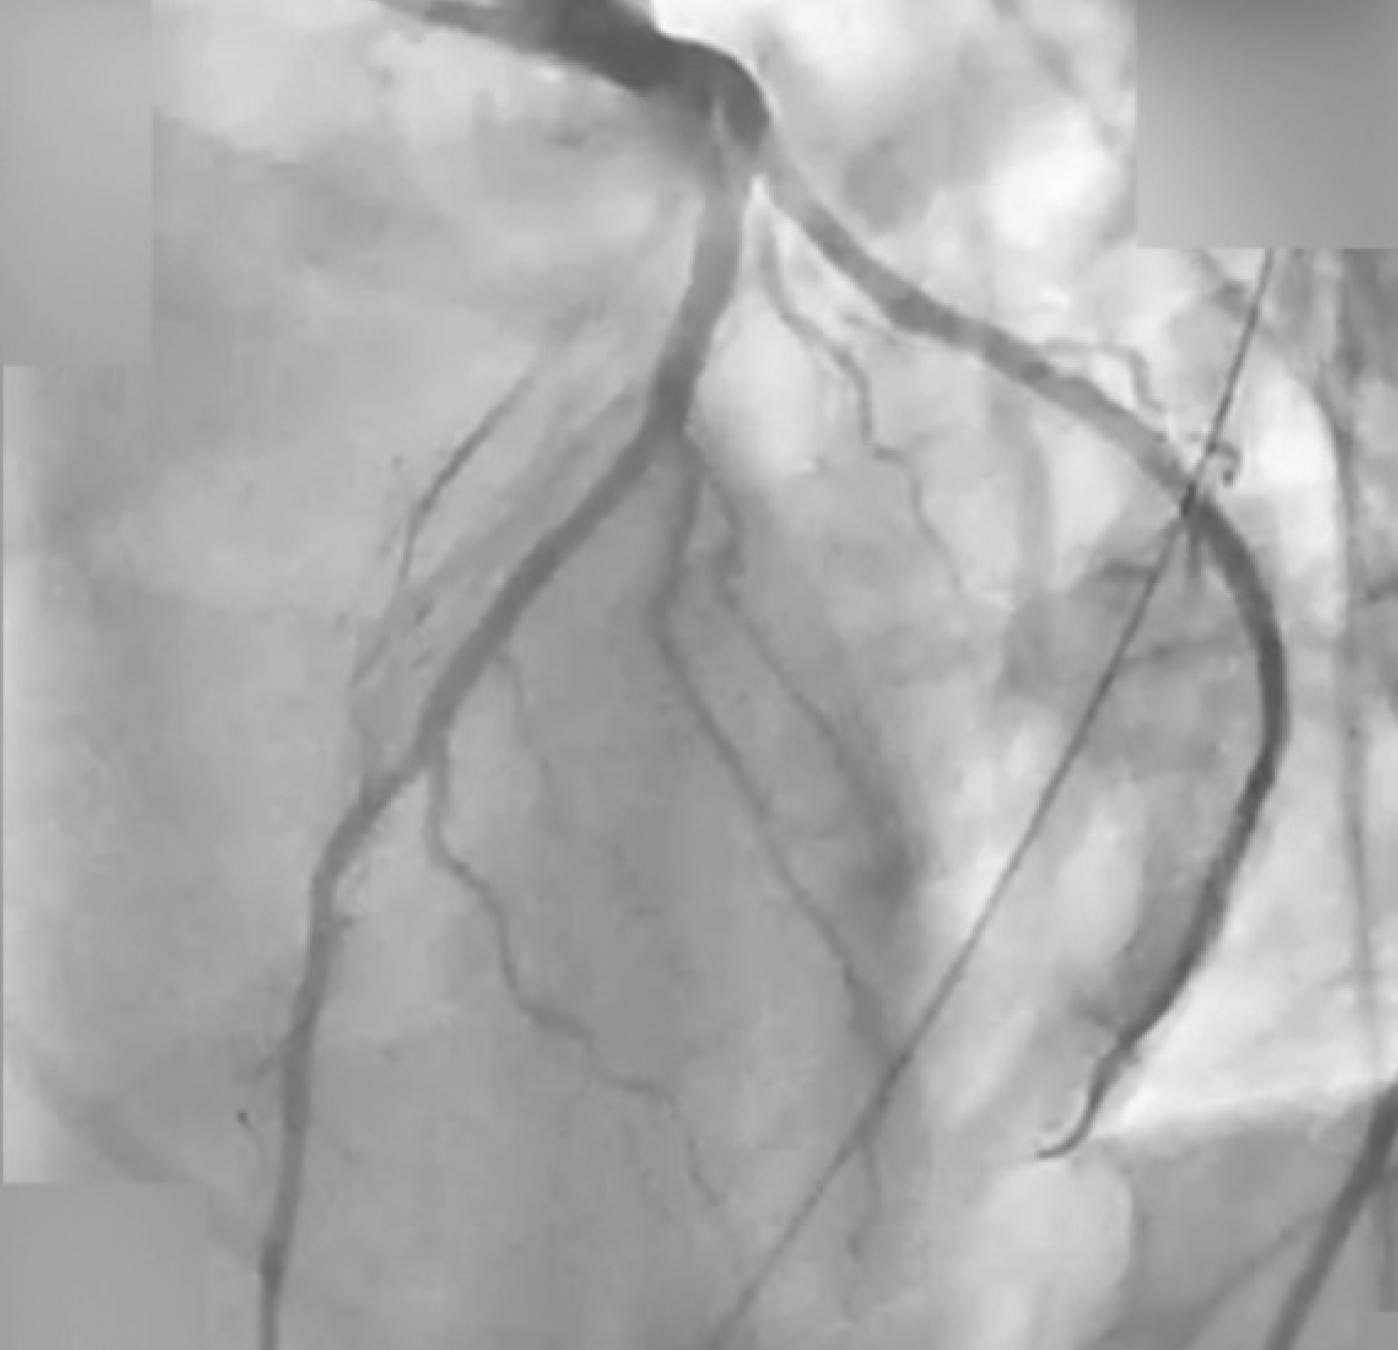

The duration of the cardiac arrest was > 45 minutes, but the emergency responders were present at onset and the patient received consistent compressions throughout. Further tests were ordered, identifying a segment just beyond the ostium of the left anterior descending (LAD) artery that was completely filled with thrombus, extending all the way to the distal vessel (Figure 1). The patient was suspected to have experienced a complete occlusion several hours earlier and had been accumulating thrombus since.

Figure 1. Initial angiogram of the LAD.

Despite initial balloon angioplasty, revascularization was unsuccessful. Next, manual aspiration catheter was utilized to address the clot burden; however, this was also unsuccessful. The team pivoted to use of the CAT RX aspiration system (Penumbra, Inc.) to deliver sustained power aspiration. In conjunction with the Penumbra ENGINE™ (Penumbra, Inc.), CAT RX removed approximately 95% of the thrombus in two passes. Subsequently, with the use of intravascular ultrasound, the patient’s LAD was stented (Figure 2). After the procedure, the patient was noted to have severely reduced LV function and hypotension. The patient was placed on vasopressors and inotropic support via intravenous infusions and, ultimately, mechanical circulatory support via an Impella device (Abiomed, Inc.). Roughly 48 hours later, the patient was taken off all circulatory support and infusions due to improved hemodynamics and recovered LV function, with repeat echocardiography demonstrating an LV ejection fraction > 65%.

Figure 2. Final angiogram after thrombectomy and stenting.